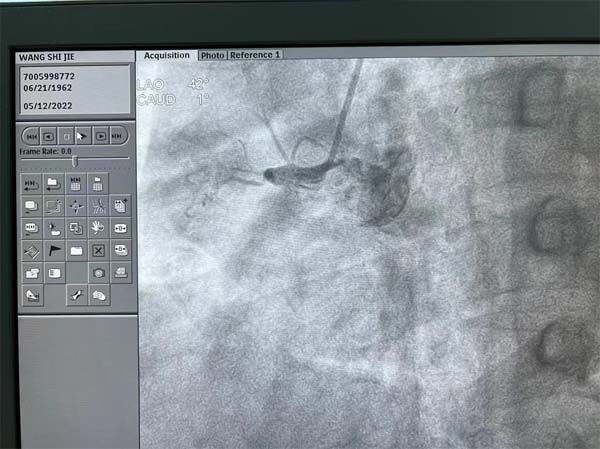

应急总医院心血管内科的疾病经常是突如其来,来势汹涌。一位59岁的男性患者在常规冠脉CT检查中发现右冠状动脉(RCA)有严重的狭窄,同时合并有十二指肠球部溃疡,患者平时没有严重的胸闷胸痛等症状,入院心电图和超声心动图检查也都正常,患者本人对检查结果还有一些意外。吴迪副院长查看该病人冠脉CT后给予了准确判断,患者RCA是完全闭塞(CTO)病变,术前一天根据患者情况制定了术中抗凝抗栓方案,患者进入导管室后实施冠脉造影,果然不出所料:RCA在近端完全闭塞,左冠脉向RCA提供部分侧支循环,RCA闭塞处有部分前向桥侧支,闭塞段超过2cm。闭塞段有部分钙化,远端血管可供登录部分比较细,增加了开通困难。吴迪副院长仔细研判造影图像,并结合冠脉CT图像,评估患者RCA闭塞血管的走形,并充分与患者本人及家属沟通,详细告知病情。

CTO病变目前还是冠脉介入治疗的难点,即便最有经验的冠脉介入医生,成功开通CTO病变的成功率也只有80-90%。吴迪副院长审时度势,迎难而上,制定前向开通方案,选择了强支撑的指引导管,在Sion导丝和微导管送至RCA闭塞处近段,逐步升级导丝,精确操控导丝,终于在微导管支撑下,多次突破闭塞处坚硬病变后,Gaia2导丝顺利到达RCA远段真腔,把微导管送至RCA远段后交换成工作导丝,从小球囊到大球囊,逐渐将闭塞病变充分预处理后置入两枚支架,RCA成功再次恢复通畅,血流恢复正常TIMI3级。手术在最短时间结束,患者平稳转至CCU监护病房,患者和家属一直悬着的心终于放了下来。患者激动地说:“心内科团队把80-90%可能变成了100%成功,太棒了!”